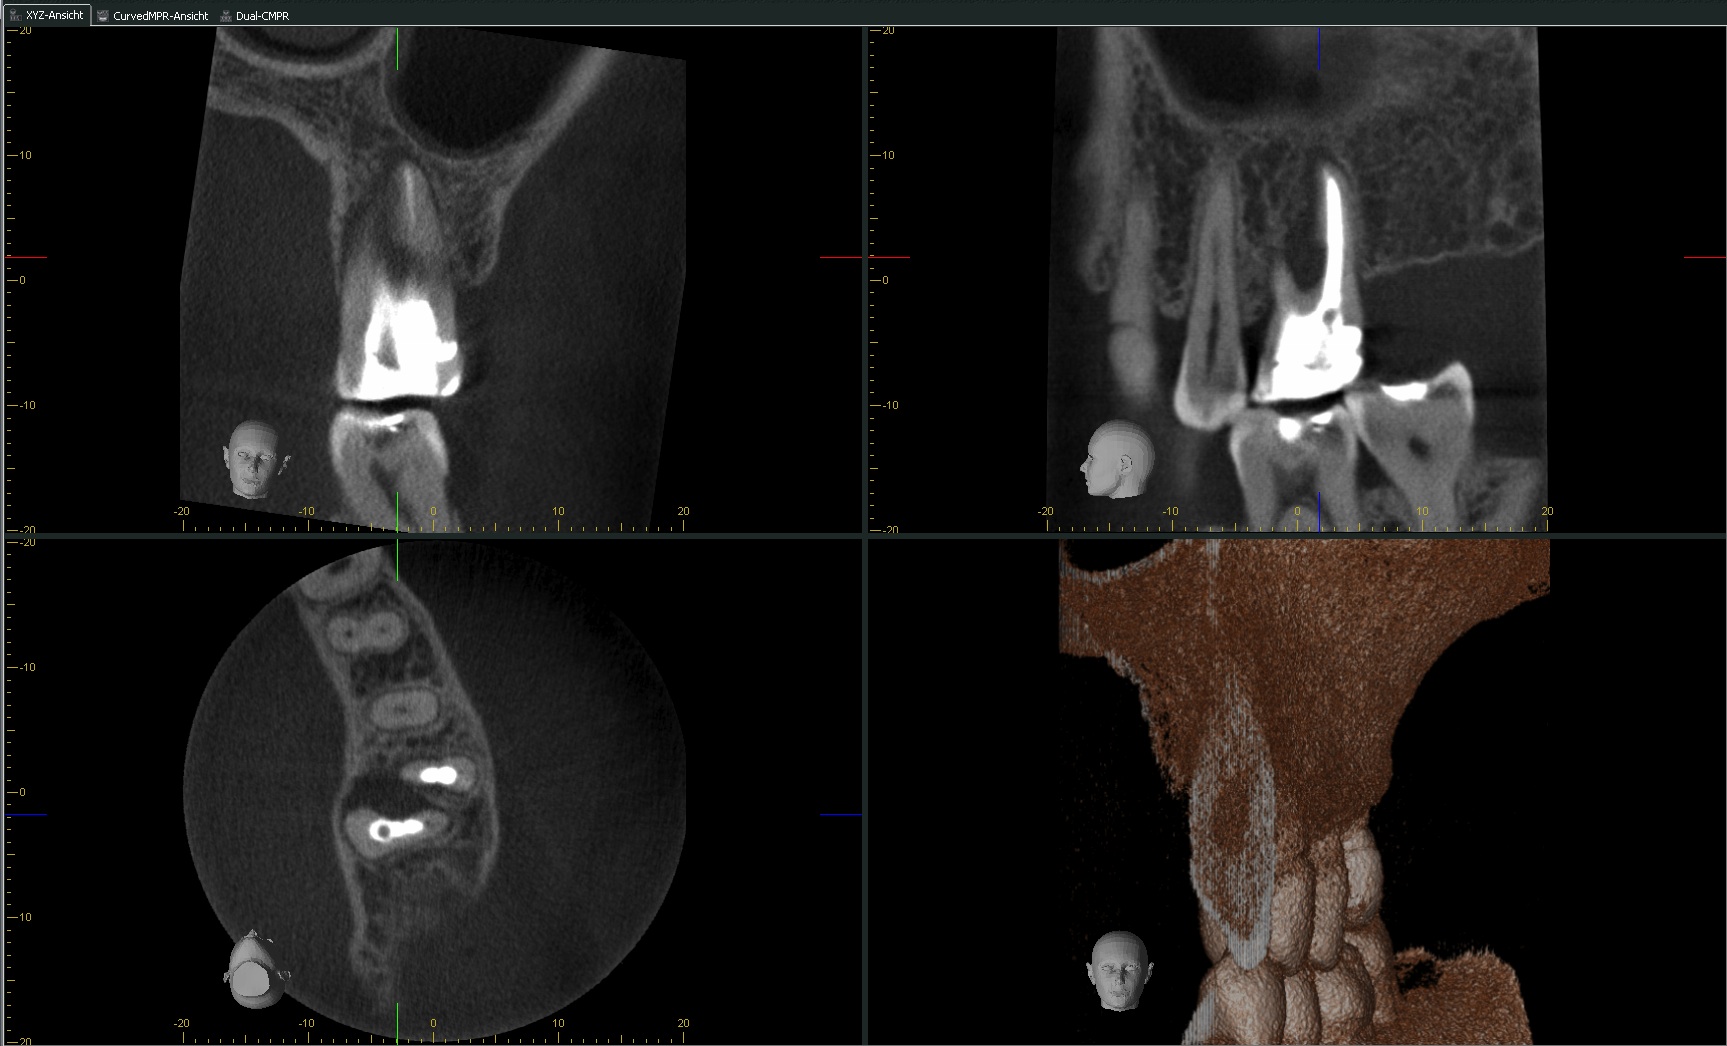

Diagnose gefragt?